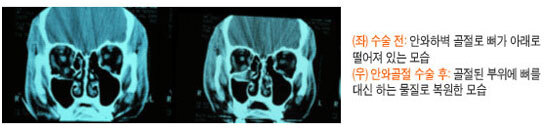

하지만 눈을 움직이는 근육과 주변 조직이 골절 부위에 끼여 안구운동장애와 복시가 있거나 골절의 크기가 커서 안구함몰 발생 가능성이 높은 경우에는 수술을 해주어야 합니다. 수술은 골절부위로 빠진 조직들을 복원시키고 다시 빠지지 않도록 인공삽입물을 삽입하여 받쳐 줍니다. - 안와골절 수술은 언제합니까?

외상으로 인한 부종이 빠지는 것을 조금 기다린 후 1-2주내에 수술하는 것이 일반적 입니다. 이유는 2주 이상이 경과하면 손상된 안와조직에서 흉터가 생기기 시작하여 수술이 어렵고 수술 결과도 나쁠 수 있습니다.